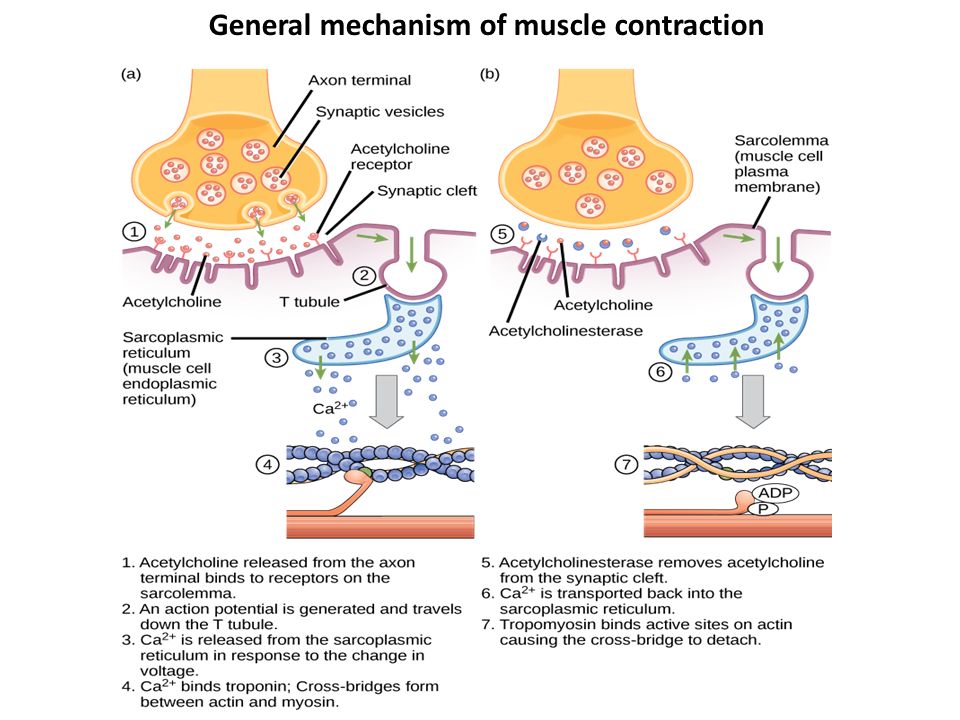

العضلات الهيكلية Skeletal Muscles هي العضلات الارادية اللي بيتحكم الانسان في انقباضها و بيستخدمها سواء بوعي و ادراك للحركة مثلا او حتى بدون ادراك زي العضلات المسؤولة عن وضعية الجسم او عن التنفس . كل عضلة و ليها توتر عضلي (Muscle Tone) بتخليها تنقبض و تبسط بشكل دائم باستثناء وقت معين اثناء النوم العميق . انقباض العضلات بيعتمد على الجهاز العصبي . القوة العضلية دي ده بتخلي العضلة جاهزة للحركة من غير ما تكون متشنجة أو مرتخية زيادة.

الاعصاب مسؤولة عن نقل الاشارات للعضلات و بتستخدم نواقل عصبية اهمها ال Acetyl Choline للانقباض في النهايات العضلية و عكسه Gamma amino butyric Acid او GABA اللي بيساعد في وقف الاشارات العصبية سواء في الجهاز العصبي المركزي او في الاعصاب الطرفية مع ادوار مهمة للAdrenaline في تحفيز الاشارات بشكل عام و ال Serotinin في زيادة ال GABA

قنوات الكالسيوم Calcium channels في جدران الالياف بتسمح بدخول الكالسيوم عند وصول الاشارة و دا اللي بيبدأ الانقباض و الماجنيسيوم في المقابل بيساعد انه يقفل القنوات دي بشكل طبيعي عشان يقلل الاستجابة الزايدة .